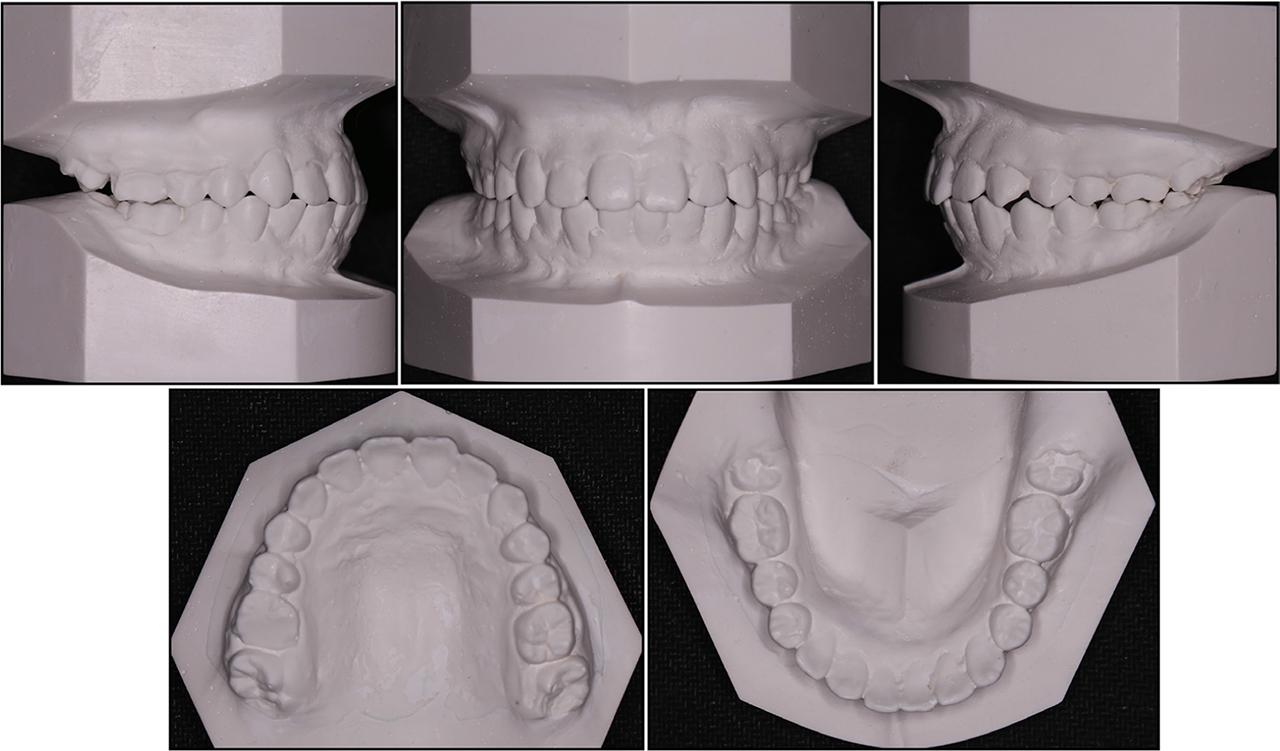

Figure 1